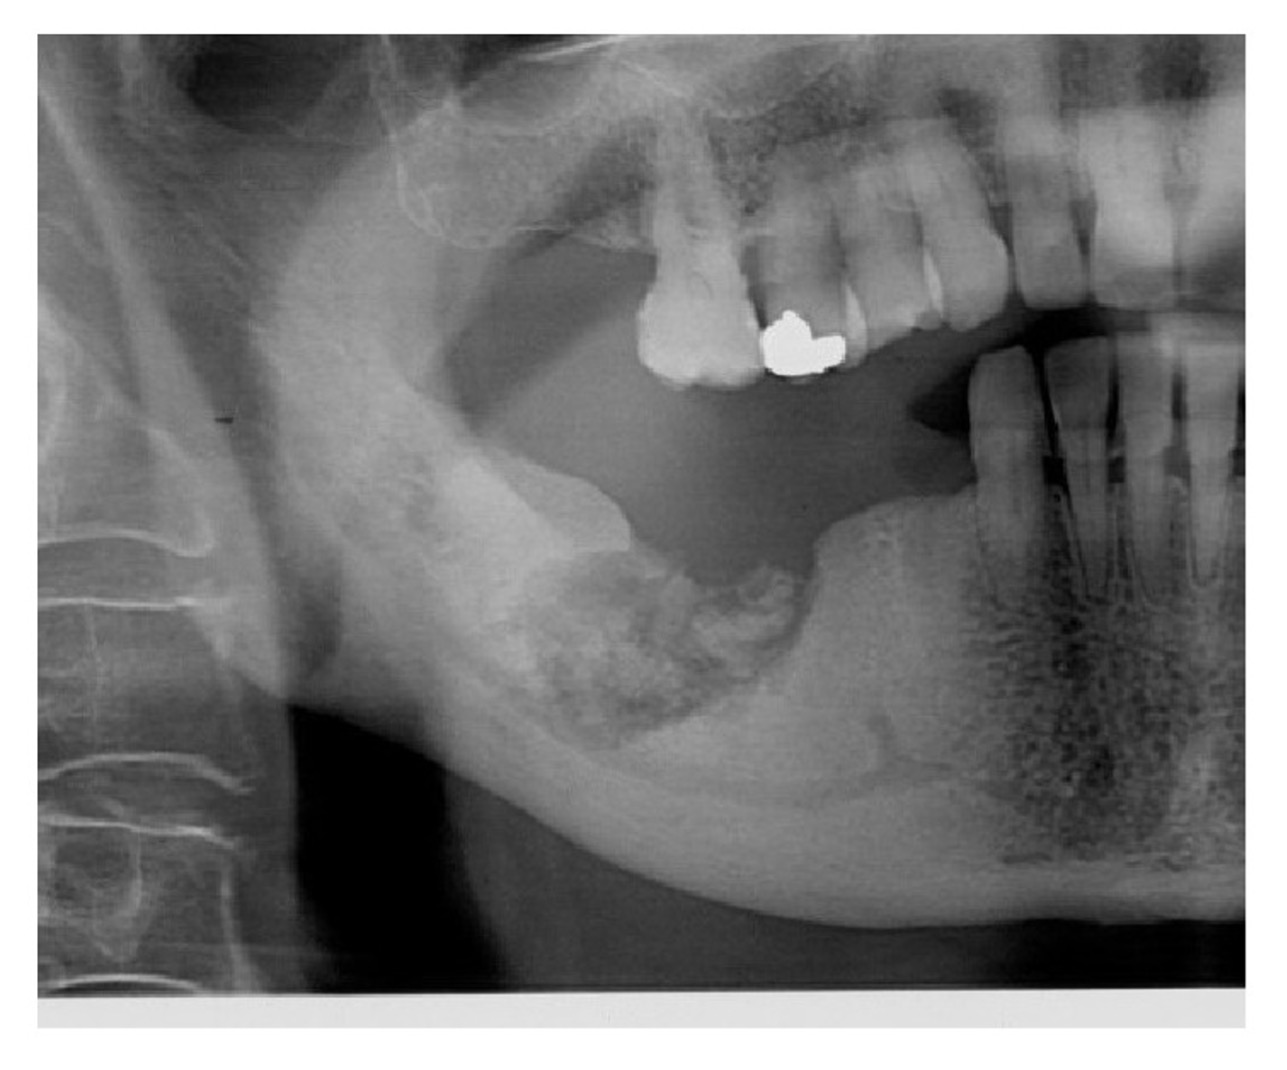

Dental Implants Osteoporosis Memphis Hernando Dental Treatment Of Osteoporosis how do these medications affect dental treatment plans? While osteonecrosis of the jaw can occur spontaneously, it more. when osteoporosis causes oral symptoms, it’s important to consult a dental specialist and a healthcare provider. a 2011 ada csa report developed by an expert panel provides potential treatment management. if you have osteoporosis or are at high. Dental Treatment Of Osteoporosis.

From www.thefacialsurgerycenter.com